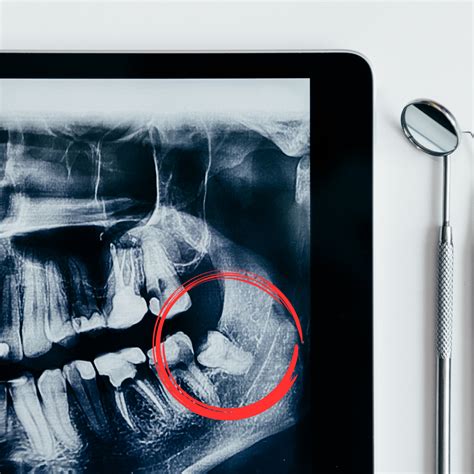

- Impactación: Si las muelas del juicio no pueden erupcionar completamente debido a la falta de espacio o una mala posición, pueden quedar impactadas en las encías o el hueso, causando dolor e inflamación.